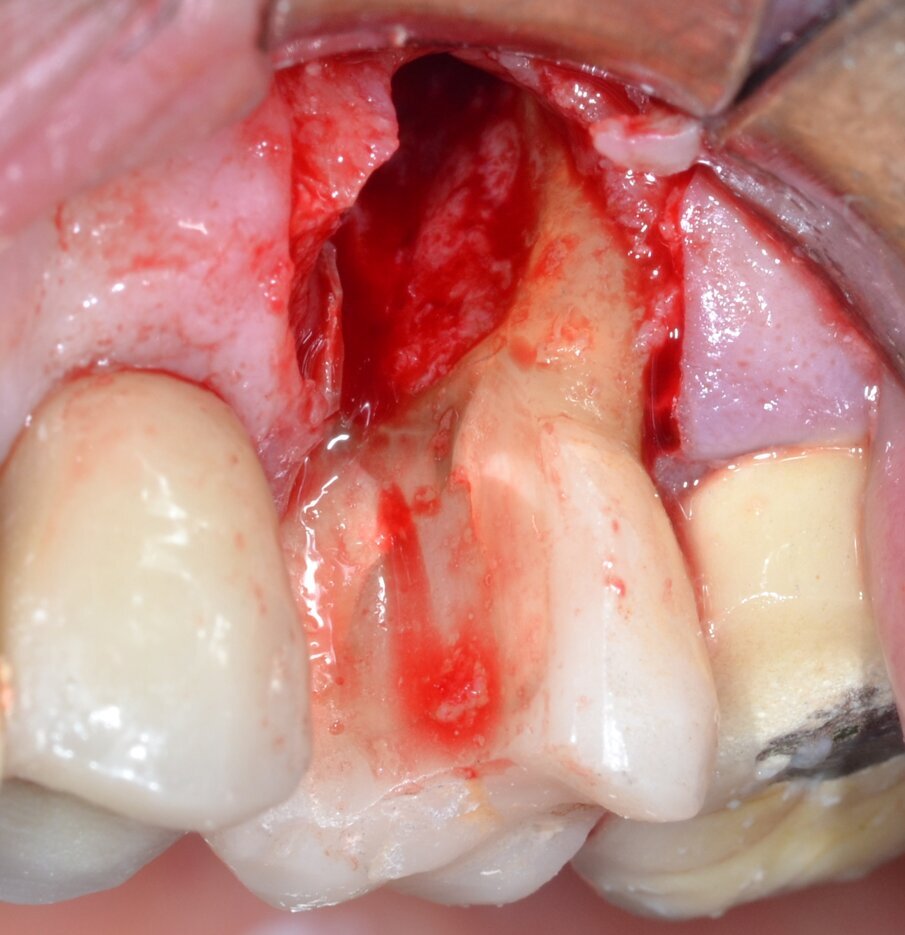

Paziente di aa 56, maschio, giunge alla nostra osservazione lamentando dolorabilità alla palpazione e alla masticazione in corrispondenza dell’elemento 1.6 sottoposto a terapia endodontica diversi anni prima. All’esame obiettivo si rileva la presenza di un’ampia raccolta ascessuale vestibolare associata a una profonda lesione parodontale nella zona della forcazione radicolare buccale (Fig. 1). Il sondaggio nel resto del cavo orale non evidenzia la presenza di altre lesioni parodontali (Fig. 2) mentre l’indagine radiografica rivela la presenza di un’ampia area di radiotrasparenza che coinvolge tutto lo spazio periapicale a partenza dalla radice mesio-buccale (Fig. 3). Sulla base dei dati clinici e radiografici acquisiti viene pertanto confermata la diagnosi di lesione endo-parodontale; nello specifico, si tratta di una lesione endodontica primaria con secondario interessamento parodontale e coinvolgimento della forcazione radicolare di Classe 3 secondo Hamp & Nyman3.

Fig. 1 - Immagine clinica preoperatoria: si evidenzia il coinvolgimento della forcazione radicolare buccale associato a una raccolta purulenta.